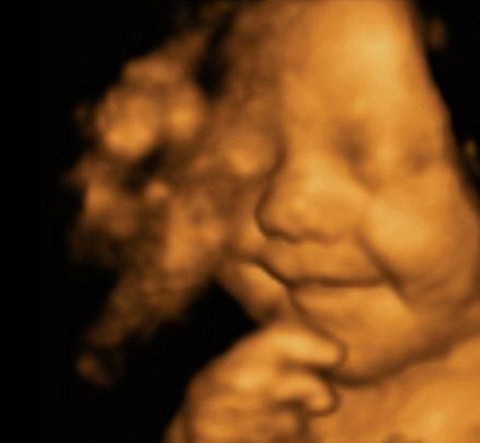

Grinning from ear to ear, this picture shows little Leo Hargreaves was rather happy with his world – even before he was born.

And his parents believe their son may be the happiest baby in Britain as he hasn’t stopped smiling since.

The remarkable image was taken from an ultrasound scan at 31 weeks.

The image is a 4D scan - increasingly popular with expectant parents to get a glimpse of how their child will look.

Rather then the grainy ‘flat’ images produced by the 2D scanners usually used by the NHS, a 4D machine stitches together pictures taken from a variety of angles to create clear three-dimensional images.

These are then recorded on video – the fourth dimension.